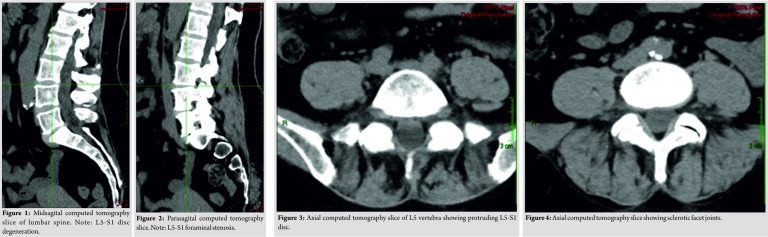

In regard to our patient, it was originally thought that the cause of the foot drop was lumbar in origin; therefore, we started our investigation with a new lumbar CT. The CT showed the known L5-S1 disc protrusion, located centrally and to the right with diffuse degenerative changes as well as sclerotic changes in facets and SIJ bilaterally (Fig. 1-4). There were no significant changes between the two scans. Since the CT findings did not explain the multi-root pathology noted on physical exam, a magnetic resonance imaging (MRI) with gadolinium injection was performed. The MRI demonstrated disc protrusions, severe right foraminal stenosis at the L5-S1 level and mild foraminal stenosis of the left side at the same level. No central spinal stenosis was observed, and the MRI signal suggested normal cord anatomy (Fig. 5-7). Since the imaging findings did not support a mechanical lumbar cause for the foot drop, an extra-skeletal cause was sought. A pelvic and hip CT scan ruled out any pelvic pathologies that could damage the peripheral nerves. A brain CT was ordered since the low back and pelvis were already ruled out as the source for the nerve damage pattern. The brain CT revealed a hemorrhage of 2.5cm in diameter with peripheral edema located in the left parietal lobe white matter (Fig. 8). MRI scan suggested an aggressive brain tumor. During the next few days, the symptoms worsened, and the patient lost her ability to move her right hand.